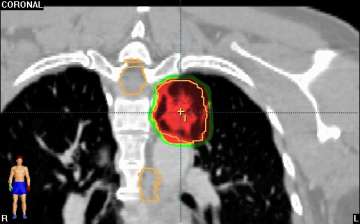

Stereotactic Body Radiation Therapy (SBRT) is a treatment procedure similar to central nervous system (CNS) stereotactic radiosurgery, except that it deals with tumors outside of the CNS. A stereotactic radiation treatment for the body means that a specially designed coordinate-system is used for the exact localization of the tumors in the body (Figure 1) in order to treat it with limited but highly precise treatment fields. SBRT involves the delivery of a single high dose radiation treatment or a few fractionated radiation treatments (usually up to 5 treatments). A high potent biological dose of radiation is delivered to the tumor, improving the cure rates for the tumor, in a manner previously not achievable by standard conventional radiation therapy (Figure 2).

Similarly, because this specialized form of radiation involves the use of multiple radiation beam angles, expert Radiation Oncologists specialized in this technique are able to safely deliver high doses of radiation, with very sharp dose gradient outside the tumor and into the surrounding normal tissue (Figure 3).

The second row shows images (axial, coronal, and sagittal) of the distribution of the radiation dose that was delivered to this area. One can see that the dose of radiation to this target is very tightly distributed to avoid as much normal tissue as possible.